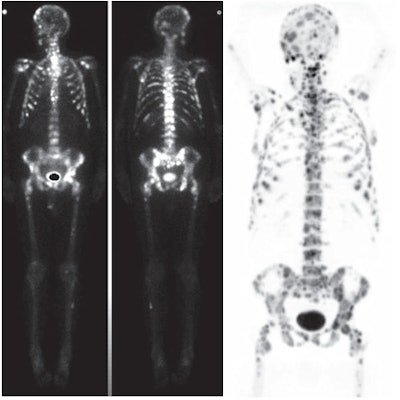

| Numerous bone metastases were detected in a 67-year-old man with prostate cancer. Bone scintigraphy (left) and NaF-PET/CT (right) images show more lesions in skull and ribs than whole-body bone MRI. Images courtesy of the American Journal of Roentgenology. |

The most common sites for metastases were in the pelvis and spine, and there were no other metastases outside of those locations, the researchers found. The patient-based analysis revealed that 16 (33%) of the 49 patients had at least one metastasis found by one of the three imaging modalities. Only five patients (9%) had skeletal metastases that were verified by both DWI-MRI and NaF-PET/CT.

NaF-PET/CT detected more true-positive lesions in four of five patients with bone metastases compared to DWI-MRI, and it detected an equal number of lesions in the fifth patient.

Two patients with uncountable bone metastases were analyzed separately. In these patients, NaF-PET/CT showed more bone metastases than DWI-MRI.